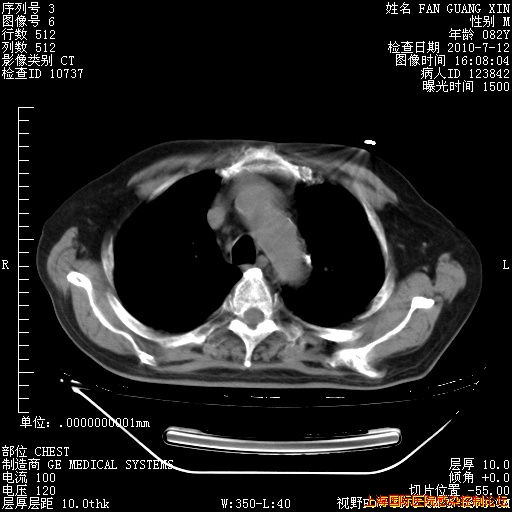

补发6月12日肺部CT肺窗

6月12日肺窗